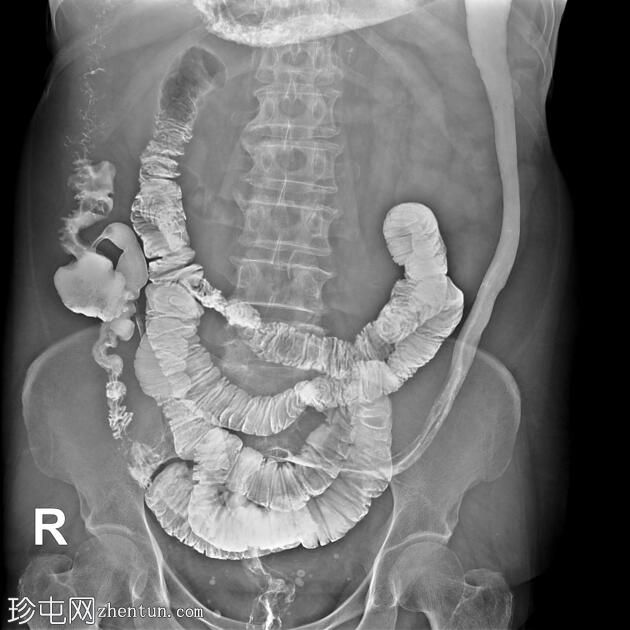

冠状位

结肠异常表现包括结肠袋皱襞消失,使其外观模糊,呈铅管样改变。

其他异常表现包括降结肠和乙状结肠肠袢狭窄,以及横结肠和降结肠多处黏膜糜烂(双对比增强图像可见)。

未见肿块或瘘管形成。

升结肠外观正常,结肠袋皱襞完整。

结肠镜检查和活检结果显示为溃疡性结肠炎,属于炎症性肠病。

结肠呈铅管状外观是慢性炎症性肠病(溃疡性结肠炎)的典型放射学表现。